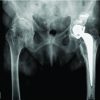

The three cases that we describe in this paper are homogenous in presentation, treatment and outcome, and therefore presented in the table below (Table 2). Pre-operative (Fig. 1-3) and post-operative (Fig. 4-6) radiographs are also included for each of the cases. 3-D reconstructed images from a computerized tomography (CT) scan for case 3 can be visualized as part of (Fig. 3).

All patients were independently mobile, active with well-fixed and well-functioning RHAs before the date of injury. All patients suffered low-energy trauma causing the fracture. All patients underwent CT scans to further delineate the fracture pattern, to assess for radiographic signs of loosening, and to assess bone stock and suitability for fixation. Intraoperatively, patients were placed on a traction table. Optimal closed reduction of the fracture was achieved using intraoperative image intensifier (II). An extended direct lateral approach to the proximal femur was used. The fascia lata was divided along its fibers and the vastus lateralis split. Fracture reduction was improved, held with 2 mm Kirschner wires placed across the fracture site, and position confirmed with II. An anatomically contoured distal femoral variable angle LCP (VA-LCP) intended for the contralateral distal femur was measured, selected, and positioned in an inverted manner (proximal and distal ends reversed). The position was checked using image intensifier. A non-locking fully threaded cortical screw was inserted distal to the fracture site to seat the plate to bone. The senior author believes that it is essential to achieve the best possible screw hold in the neck, and therefore accept to some extent that the plate distally may not sit perfectly centered over the shaft of the femur. Shaft screws can be inserted distally through a minimally invasive plate osteosynthesis technique if desired. All patients were asked to partially bear weight on the operated side for 8 weeks. The time to radiographic union and the time to discharge from physiotherapy with achievement of previous level of function were recorded for two patients. One patient, case 3 (Fig. 3, 6), was lost to follow-up as she moved out of the country.